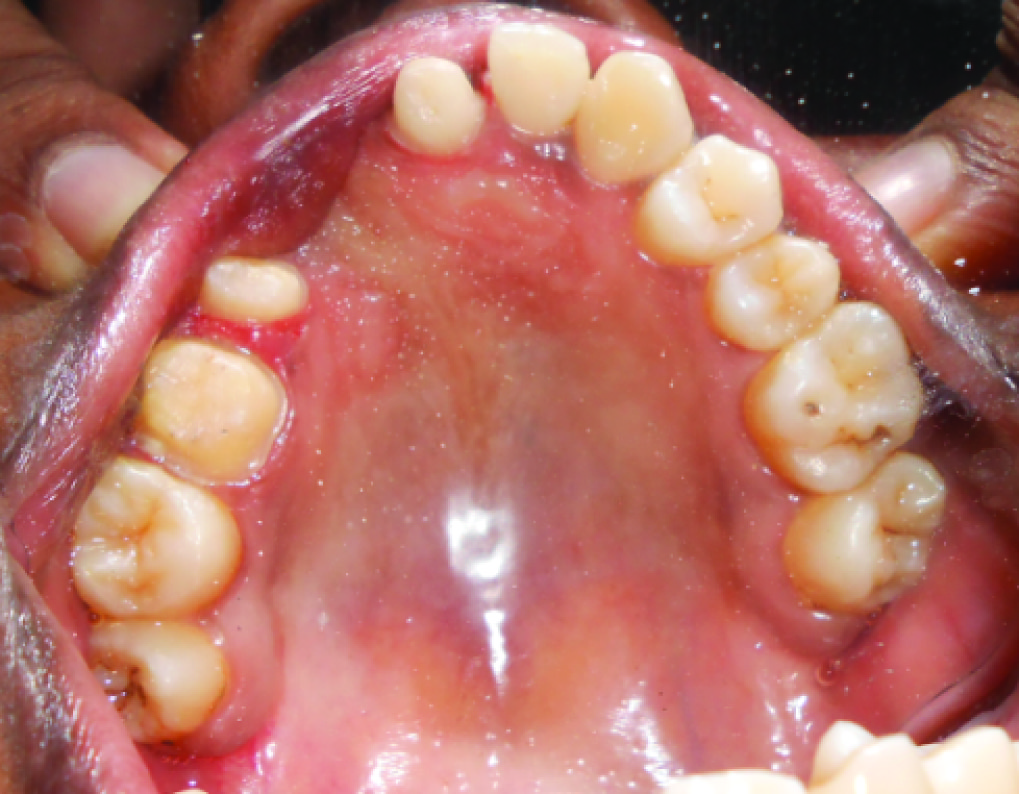

A 21-year-old female patient came to the Department of Prosthodontics and Implantology, Thai Moogambigai Dental College and Hospital, Chennai, India with a complaint of unaesthetic appearance due to missing upper front tooth for which she wanted fixed replacement of her missing front teeth. Patient gave a history of trauma when she was four years of age which was not attended immediately. The patient developed a swelling after three months of injury following which 61,62,63,64 were extracted and were not replaced.

On clinical examination there was congenital absence of 21,22,–23,24 and severe midline shift of right side anterior teeth towards the left side. The edentulous ridge in relation to 21,22,23,24 appeared narrow and resorbed. Due to the missing anterior teeth, 25 were also rotated towards the edentulous space. Crowding of the lower anterior teeth was noted [Table/Fig-1].

The patient’s ridge defect was classified based on Seibert’s nomenclature [1] and Struder et al., quantitative assessment of bone defects [2]. Intraoral clinical picture of the patient showed that there was loss of residual ridge horizontally as well as vertically at the edentulous space in the maxillary arch and hence it was categorized as Seibert’s Class III type of ridge defect, thereby clinically making the implant placement a questionable procedure. The patient was not willing for surgical bone grafting along with implant placement. A conventional fixed partial denture was also not possible due to the severity of the bone defect.